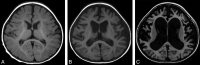

Fig 5.

Type 5. Progressive brain atrophy. Sequential change of brain MR imaging of patient 27 with an ATRX mutation in int 35 (c.7200 + 4A>G, p.L2401fs) at 6 months (T1WI) (A), 14 months (T1WI) (B), and 34 months (FLAIR) (C).